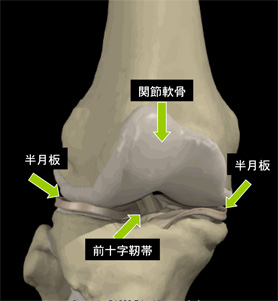

膝の組織について

膝の組織をご説明します。

この絵を参考にしていただければ、下記の障害について、どの部分が障害を受けているのかわかりやすいと思います。

半月板は弾性に富んだ線維軟骨でできていて、大腿骨と脛骨の内側、外側のすきまにあり、関節の適合性を良くして安定性を与え、荷重ストレスを吸収分散するクッションの役目もしている三日月形のものです。